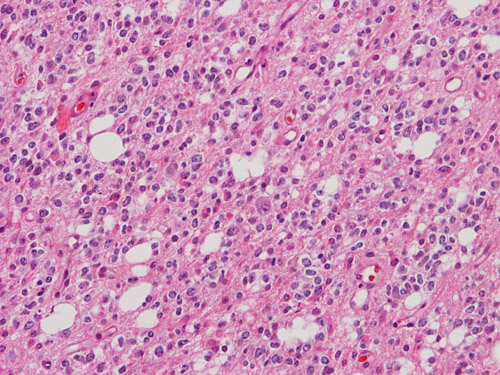

6.    Which of the following features will be helpful in the diagnosis and prognostic assessment of the tumor illustrated below which is obtained from the frontal lobe of a 32 year-old man?  Answer

Please click on icon to see full sized image.

A.  Positive immunoreactivity for glial fibrillary acidic protein (GFAP)

B.  Mutation of isocitrate dehydrogenase (IDH) 1 and lost of chromosome 1p and 19q

C.  Weakly positive for synaptophysin staining

D.  Demonstration of BRAF-KIAA1549 fusion

E.  Demonstration of gemistocytic astrocytes